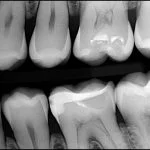

3 Key Differences Between Extraoral Dental Bitewings and Intraoral Dental Bitewings